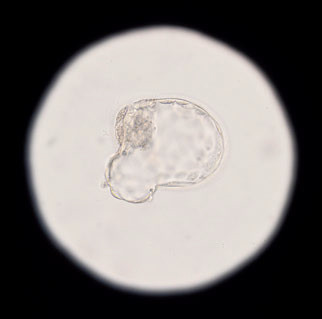

Для женщины программа ЭКО чаще всего начинается со стимуляции овуляции: нужно получить несколько яйцеклеток, ведь впоследствии не все эмбрионы могут оказаться жизнеспособны.

«Обычно в одном менструальном цикле созревает только один фолликул. Чтобы запустить в рост сразу несколько (в среднем 5–15), репродуктолог при помощи гормональных препаратов проводит стимуляцию суперовуляции. Препараты, их дозировки, время введения подбираются лечащим врачом строго индивидуально», — подчеркивает Юлия Фетисова, врач-репродуктолог клинического госпиталя MD GROUP Группы компаний «Мать и дитя».